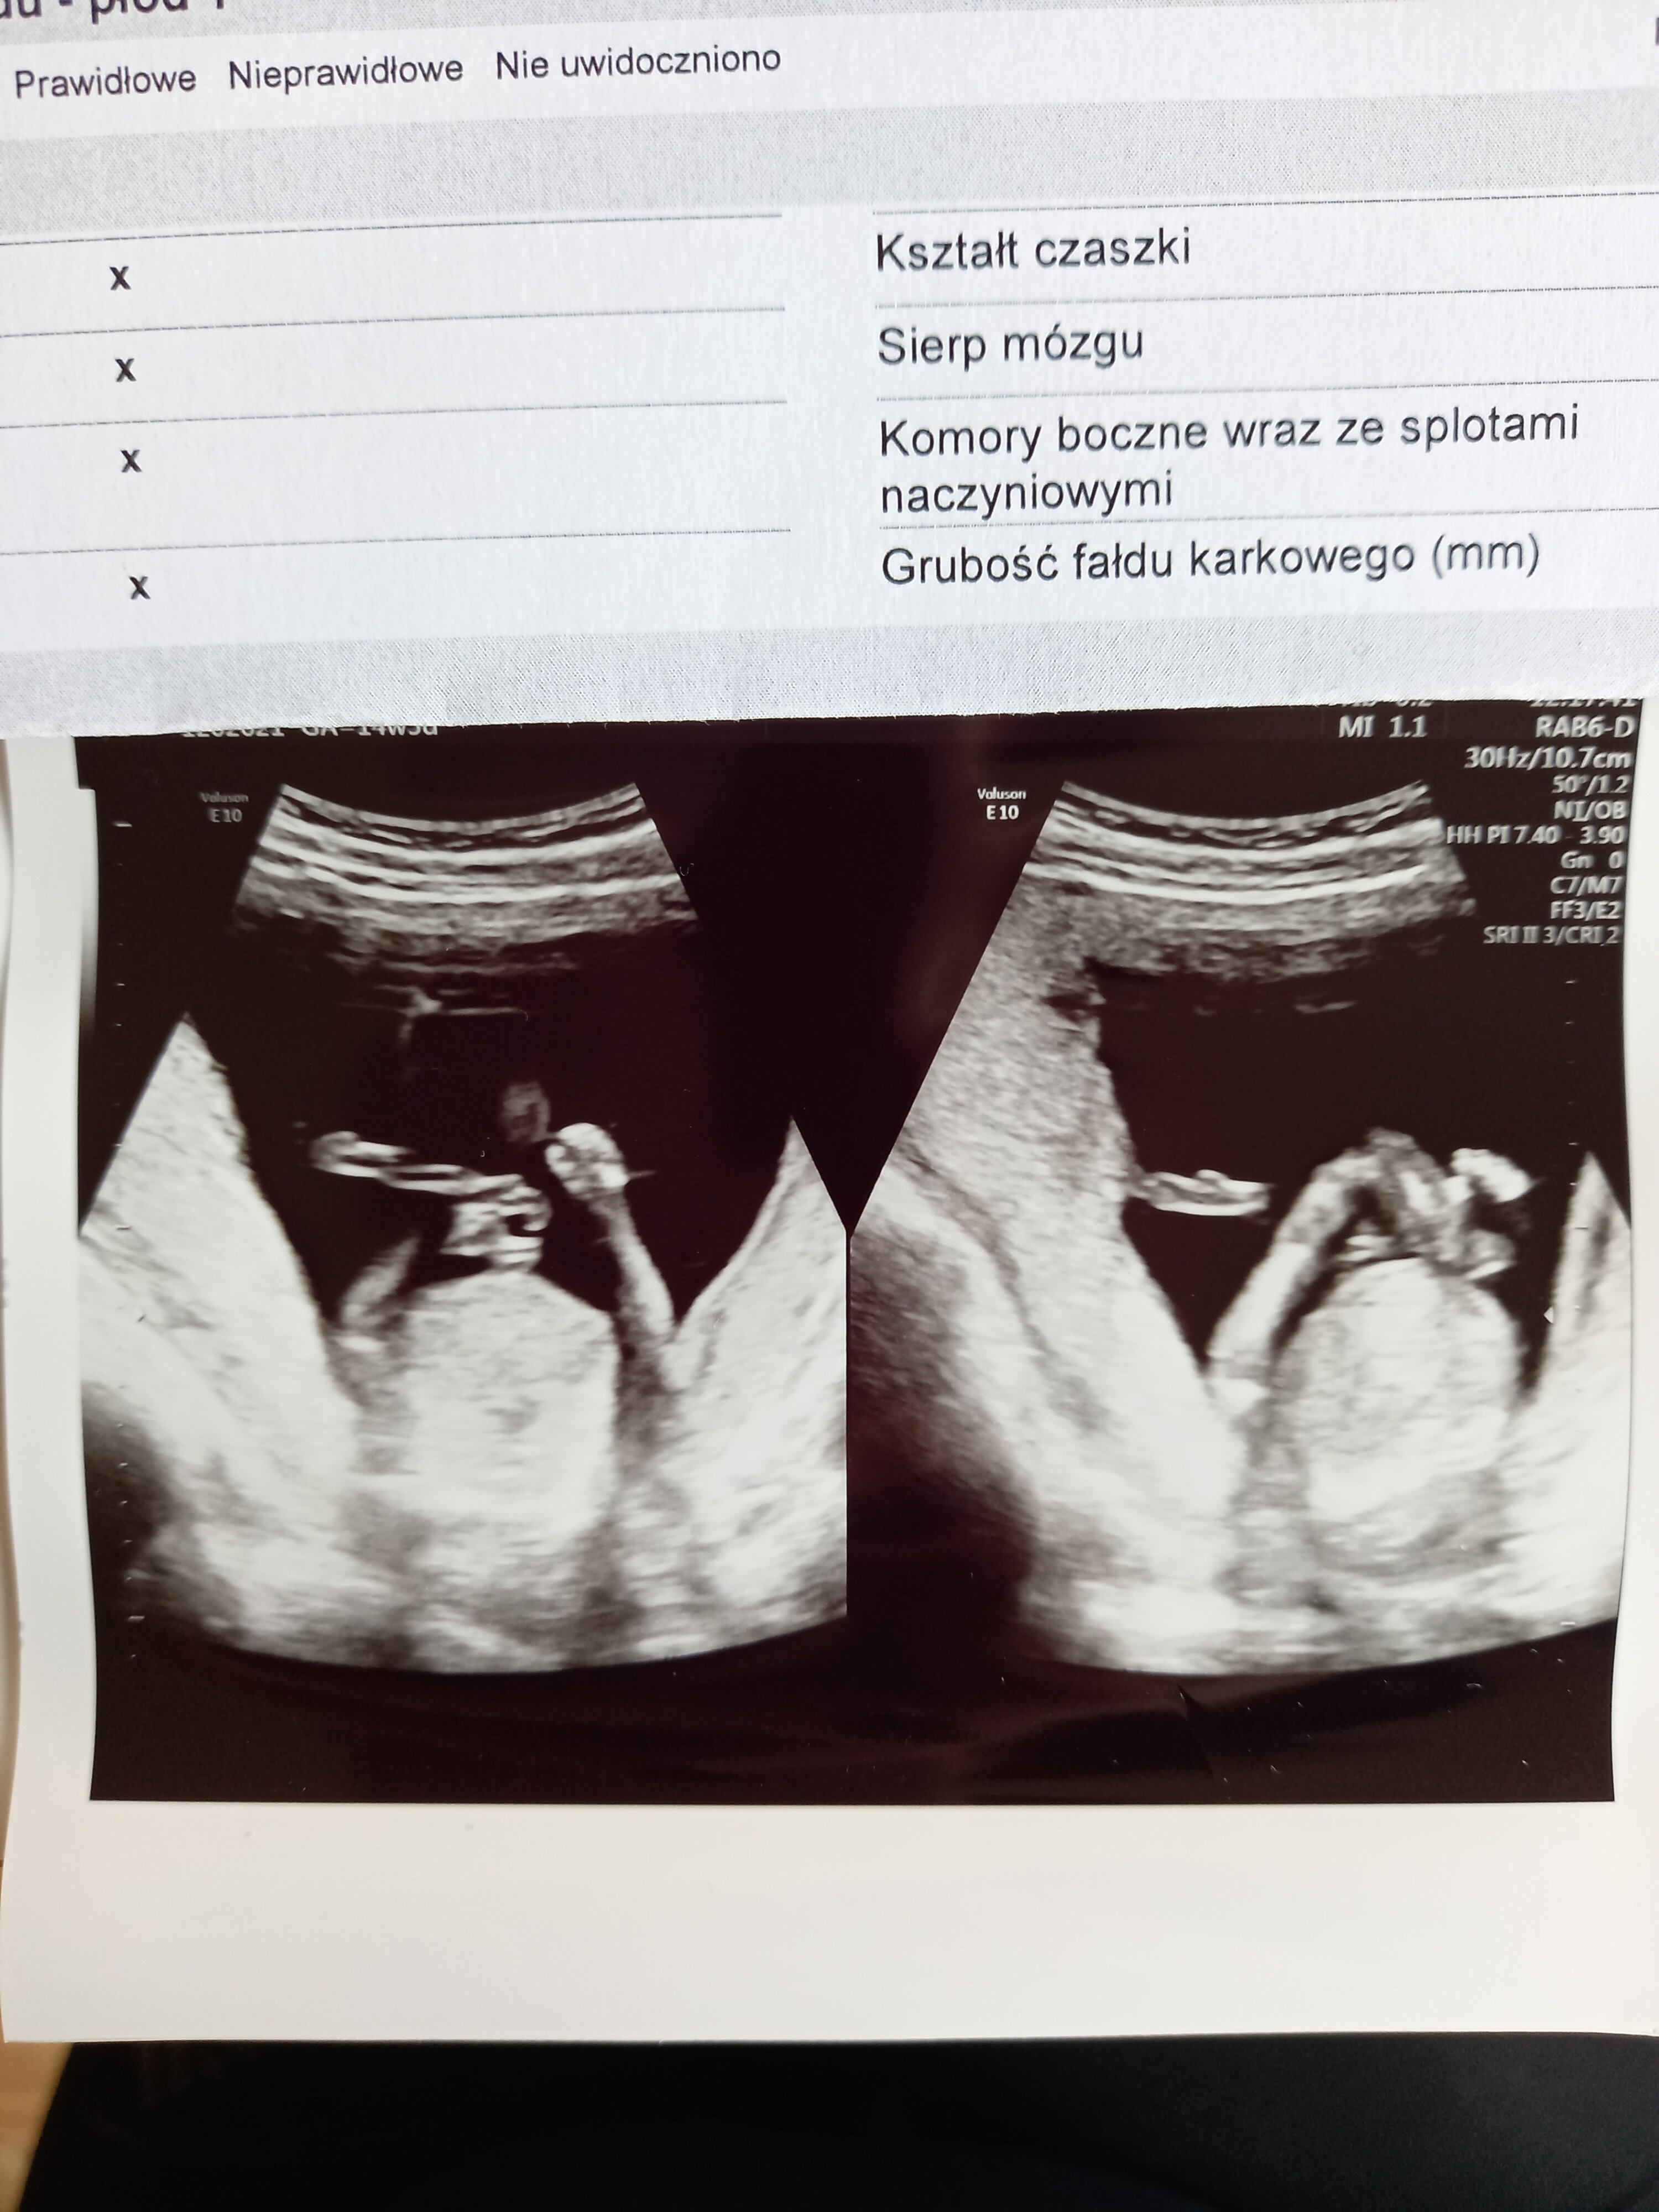

Ja już po wizycie

moja Zuzia okazała się synkiem

krwiak się zmniejsza. Pani dr mówi żeby zapomnieć że on tam wogóle jest. Niestety nie mam żadnego ładnego zdjecia, tylko takie gdzie macha rączkami

termin wedlug usg na 25.04. Ale liczę że to będzie maj (córkę urodziłam 2 tyg po terminie). I tak mam z om na 1 maja. Pozdrawiamy

[emoji1787][emoji1787] gratulacje [emoji16]Ja już po wizycie [emoji846][emoji846] moja Zuzia okazała się synkiem [emoji4][emoji28] krwiak się zmniejsza. Pani dr mówi żeby zapomnieć że on tam wogóle jest. Niestety nie mam żadnego ładnego zdjecia, tylko takie gdzie macha rączkami [emoji4] termin wedlug usg na 25.04. Ale liczę że to będzie maj (córkę urodziłam 2 tyg po terminie). I tak mam z om na 1 maja. Pozdrawiamy [emoji9]

No dziś pięknie pokazał jajeczka[emoji1787][emoji1787] gratulacje [emoji16]

Dokładnie.ja wg USG 14+4 to jesteśmy dosyć blisko![]()